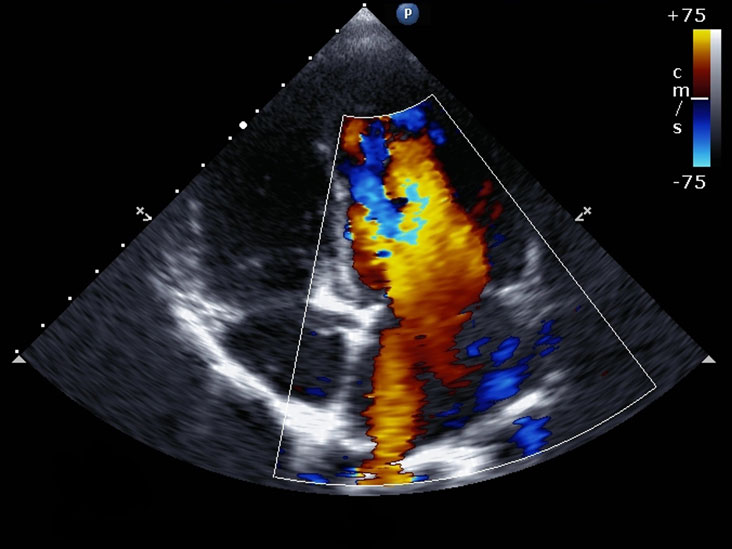

An echocardiogram (echo) is an ultrasound scan of the heart and nearby blood vessels to assess their structure and function.

For an echocardiogram, you’ll be offered a chaperone, asked to removed clothing covering the upper half and given a gown open at the front. You’ll be asked to lie on the couch. Three small stickers will be attached to your chest to monitor your heart rate and rhythm during the test. You usually will be asked to lie on the left side. This is to improve the image quality of the echocardiogram. Images will be taken by placing the ultrasound gel and probe on your chest.